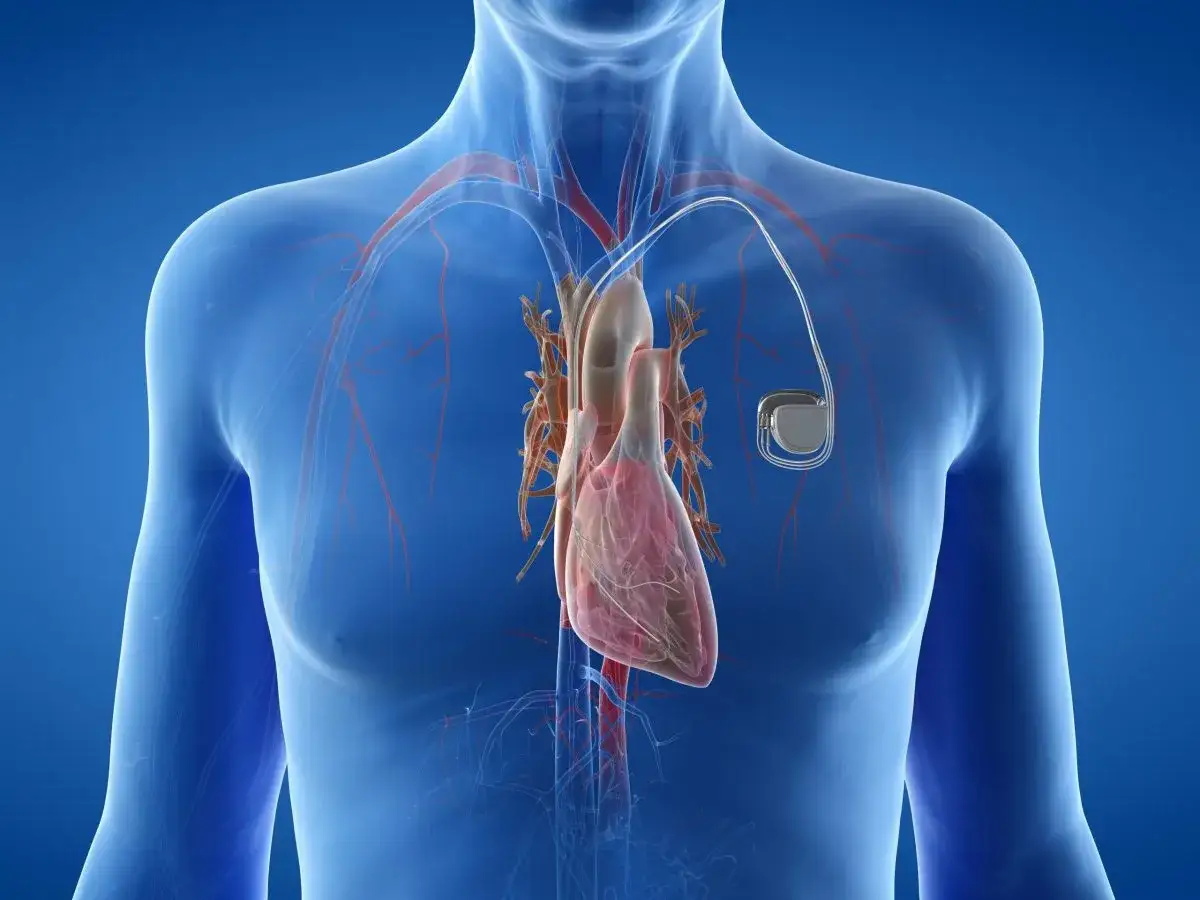

Wszczepialny kardiowerter-defibrylator (ICD) to znacznie więcej niż tylko zaawansowany rozrusznik serca. To skomplikowane urządzenie medyczne, które nieustannie monitoruje rytm Twojego serca i, co najważniejsze, interweniuje w przypadku wykrycia groźnych arytmii. Jego podstawowa budowa obejmuje generator impulsów, często nazywany potocznie "puszką", który zawiera baterię i zaawansowaną elektronikę, oraz elektrody. Te cienkie przewody są wprowadzane do serca i to właśnie one są oczami i uszami urządzenia, przekazując informacje o jego pracy.

- Urządzenie składa się z generatora impulsów ("puszki") i elektrod wprowadzanych do serca.